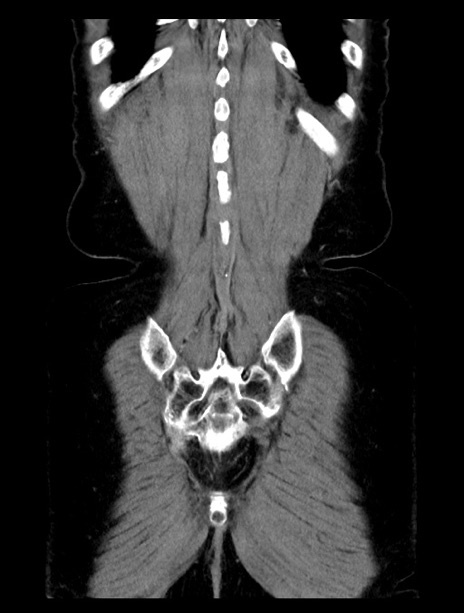

横断像

【症例】70歳代女性

【主訴】下腹部痛・嘔吐

【現病歴】2日前より腹痛あり。昨日嘔吐あり。症状改善しないため来院。

【既往歴】胃GISTに対して胃部分切除後。

【身体所見】BT 37.1℃、BP 128/77mmHg、腹部:平坦・軟、下腹部に圧痛あり。

【データ】WBC 10200、CRP 0.31